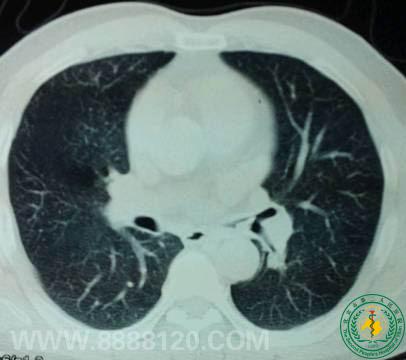

呼吸一科成功钳夹支气管异物一例

呼吸一科成功钳夹支气管异物一例3937